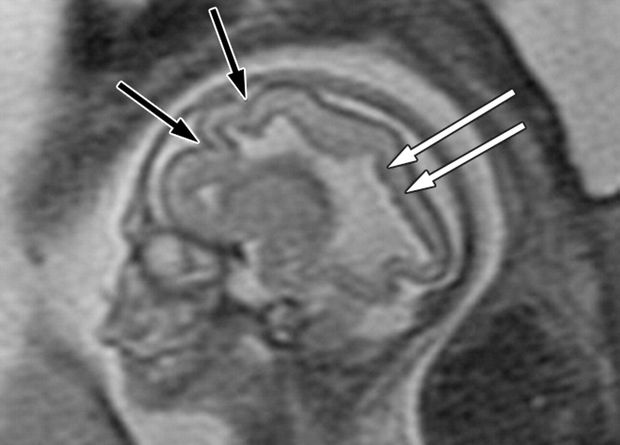

Для этого они собрали данные из более ста проектов, в которых суммарно участвовали 101 457 человек, от четырехмесячных эмбрионов до столетних долгожителей. Исследователей интересовали четыре метрики: объем серого вещества в коре головного мозга, объем подкоркового серого вещества, общий объем белого вещества и объем спинномозговой жидкости (которая содержится в том числе в желудочках головного мозга). Из этих